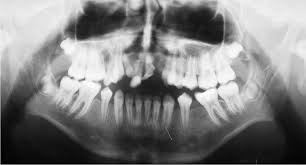

A brief mention will be made of yet another positional anomaly of the canines: transmigration. Transmigration is exclusive of the mandibular perma- nent canine. In this anomaly, the canine from one side of the arch migrates through the bone and erupts on the opposite side of the arch. For instance, the right mandibular canine migrates through the sympheseal area and erupts into the arch in the place where the left canine usually erupts. This anomaly could present a complex clinical problem, because the clinician will be facing a situation where the canine from one side appears to be missing, while the opposite side may appear to have a supernumerary canine.15 Like so many dental problems, this last anomaly is best detected by radiographic examination. If detected early enough, its treatment may not be too difficult. This will reinforce the urging of a mature teacher to obtain and examine our patients’ records with care and attention to detail.